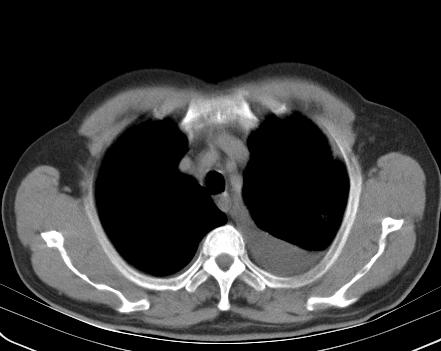

以下是引用老爱克斯新网客在2008-7-31 6:30:00的发言:[br]左肺上叶大片状病灶,左肺上叶支气管狭窄呈鼠尾状,左肺门增大,纵隔内见肿大淋巴结,左侧胸腔积液,余肺清晰。左肺中心型肺癌淋巴结转移,

以下是引用zjb在2008-7-31 6:32:00的发言:[br]左侧中心性肺癌 阻塞性肺炎 肺不张 胸腔积液 建议气管镜

以下是引用zjzjr在2008-7-31 8:45:00的发言:[br]考虑左侧中心性肺癌伴阻塞性肺炎,左肺上叶肺不张,纵隔淋巴结转移;左侧胸腔积液。建议行纤支镜检查。

以下是引用sdzyy在2008-7-31 8:47:00的发言:[br]病灶较治疗前有所进展,胸水增多, 左侧中心性肺癌 并 阻塞性肺炎 肺不张 胸腔积液 可能性大; 建议气管镜检查。 [br] [br]